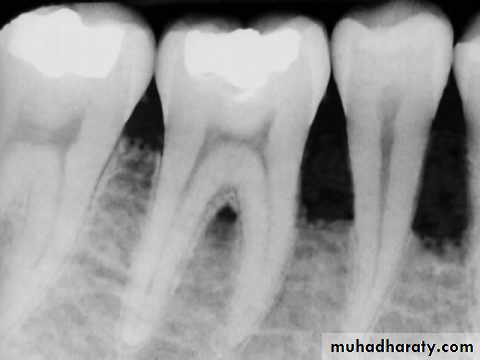

Variability in the radiographic expression of an osseous pathosis has much to do with the relative location of the root of the tooth and how it is oriented with respect to the cortical and cancellous bone

Radiographic changes from bone loss will not be detected if the loss is only in cancellous bone. However, the radiographic evidence of pathosis will be observed once this bone loss extends to the junction of the cortical and cancellous bone.

The apices of most anterior and premolar teeth are located close to the cortical-cancellous bone junction.

Therefore, periapical pathosis from these teeth is exhibited sooner on the radiograph

By comparison, the distal roots of mandibular first molars and both roots of mandibular second molars are generally positioned more centrally within the cancellous bone, as are maxillary molars, especially the palatal roots Periapical lesions from these roots must expand more before they reach the cortical-cancellous bone junction and are recognized as radiographic pathosis

For these reasons, it is important not to exclude the possibility of pulpal pathosis in situations in which there are no radiographic changes